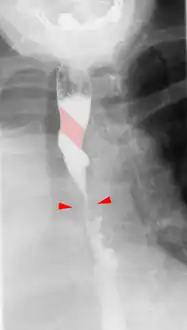

Tape-like impression of the esophagus caused by aberrant subclavian artery. Below (arrows) narrowing of the esophagus by a tumor that is causing the swallowing problems. -